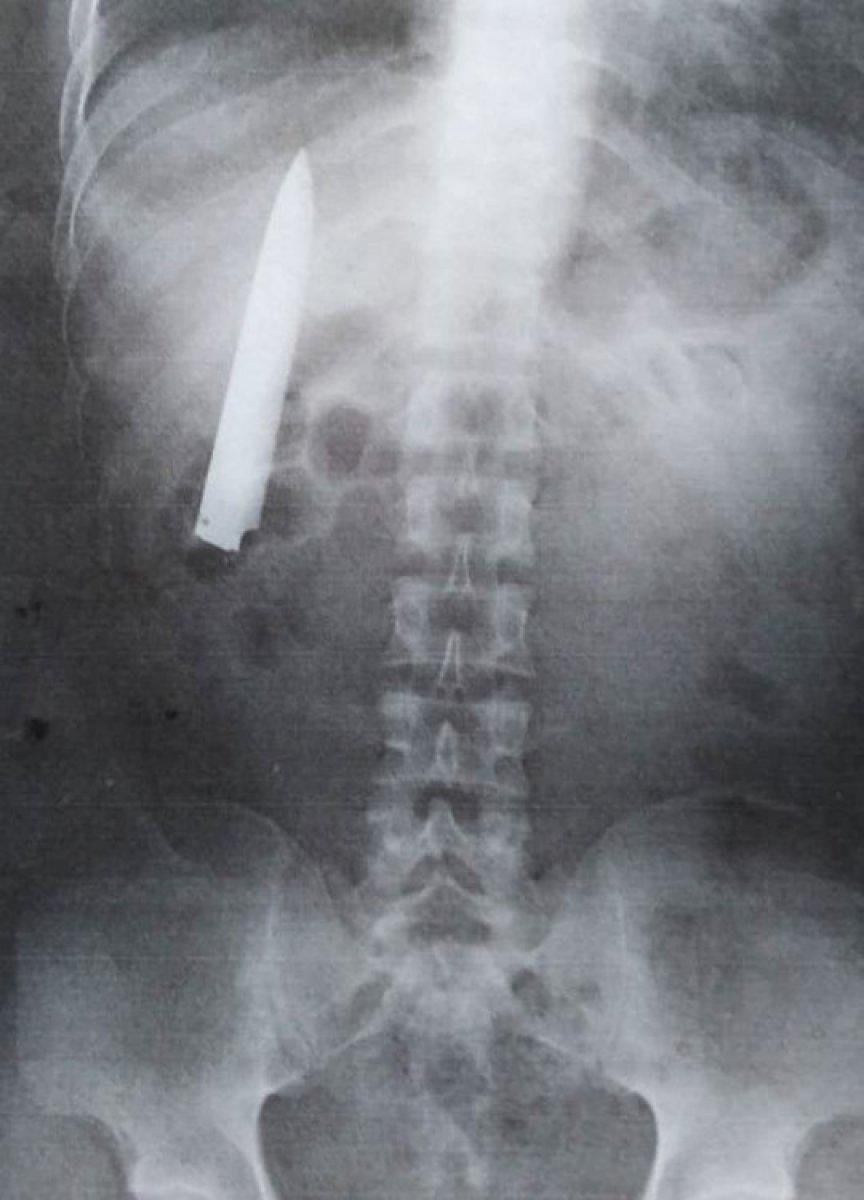

RÖNTGEN ÇEKİLMEDEN YARAYA MÜDAHALE EDİLDİ

Tomao hastaneye kaldırılırken, buradaki doktor önce röntgen çekmek yerine doğrudan yaraya müdahalede bulundu.

Filipinli genç ile ilgili gerçek, iş başvurusu sırasında talep edilen röntgen belgesinde ortaya çıktı.

25 yaşındaki Tomao, 15 ay önce yaşadığı olayda bıçağın akciğerlerine yakın bir yerde saplandığını öğrenince şaşkına döndü.